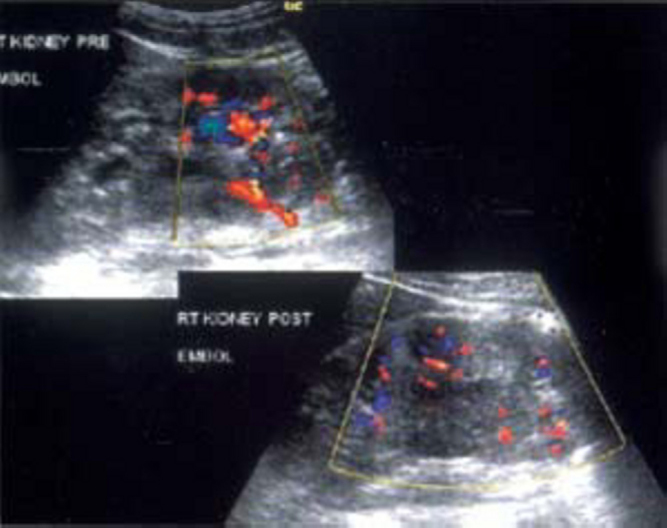

Pseudoaneurysm at inguinal region following catheterization, presents with a painful, pulsating enlarging groin mass, associated with a thrill and/or bruit. Pseudoaneurysm in kidney presents with recurrent and intermittent hematuria following procedures like PCNL, renal biopsy and occasionally after surgery. Coil embolisation is an effective modality in shutting down the offending pseudoaneurysm (Fig. 3A, Fig. 3B).

Fig. 3A.

Color doppler of right kidney in an adult male presenting with recurrent hematuria following PCNL shows pseudoaneurysm. Post embolisation color doppler images reveal obliteration with regression in size.

Fig. 3B.

DSA of right kidney in same patient shows pseudoaneurysm. Post embolisation DSA images reveals obliteration of pseudoaneurysm. Note the distribution of coils along the renal artery on CT abdomen.